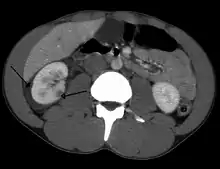

Abdominal trauma resulting in a right kidney contusion (open arrow) and blood surrounding the kidney (closed arrow) as seen on CT | |

Spleen

Spleen is the most common cause of massive bleeding in blunt abdominal trauma to a solid organ. Spleen is the most commonly injured organ. A laceration of the spleen may be associated with hematoma.[13] Because of the spleen's ability to bleed profusely, a ruptured spleen can be life-threatening, resulting in shock. However, unlike the liver, penetrating trauma to the spleen, pancreas and kidneys do not present as much of an immediate threat of shock unless they lacerate a major blood vessel supplying the organs, such as the renal artery.[5] Fractures of the left lower ribs are associated with spleen lacerations in 20 percent of cases.[9]